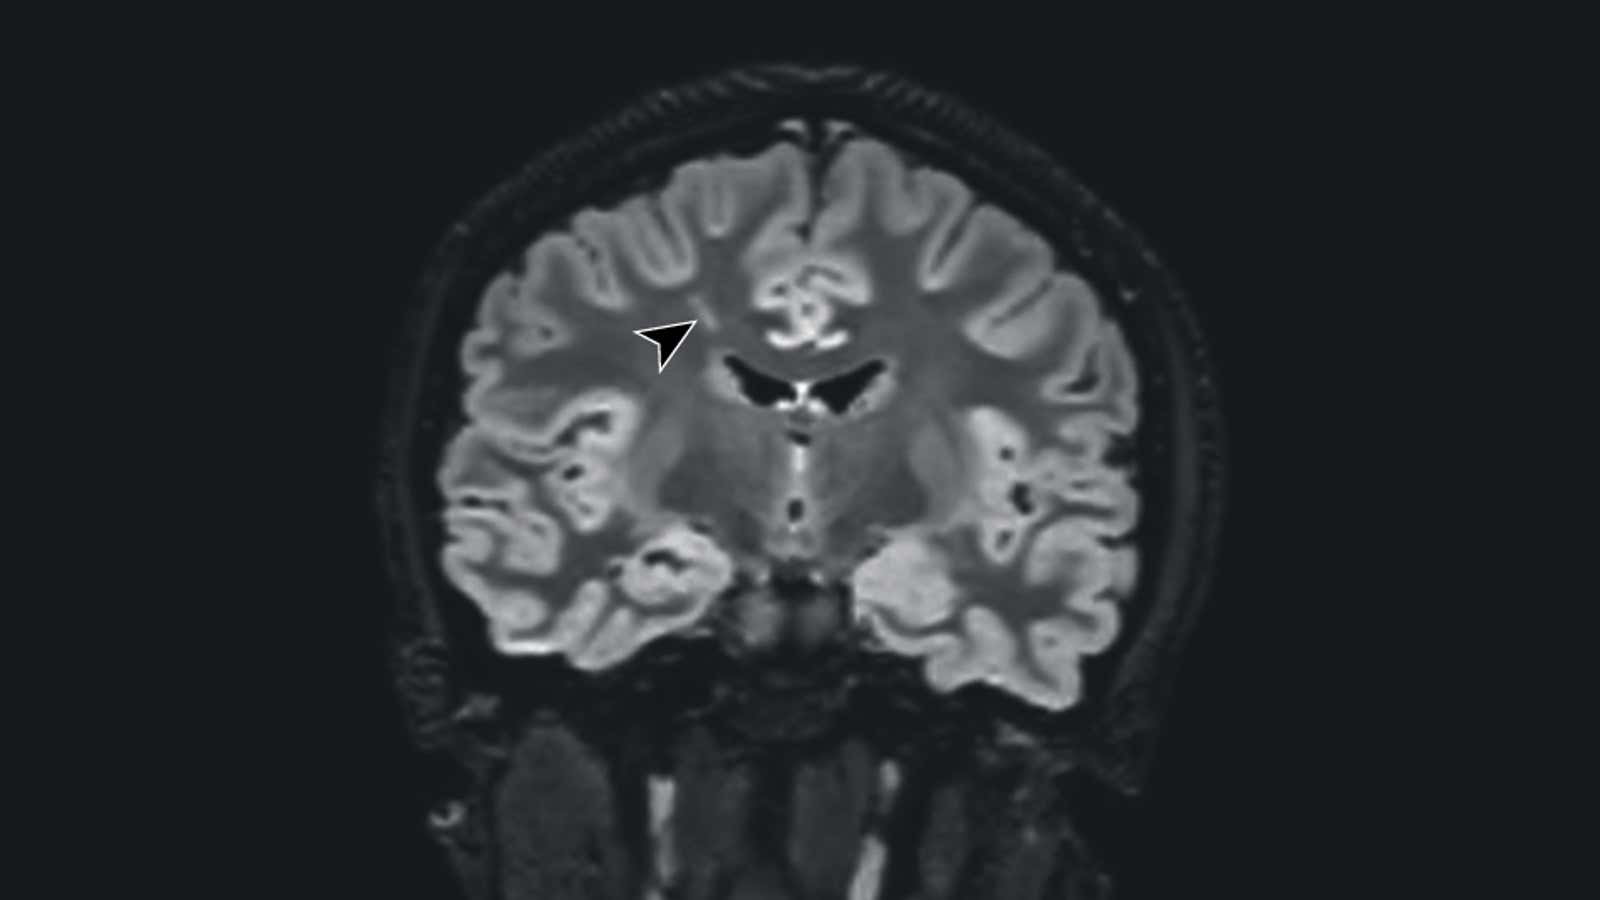

In late October, doctors in California published a case report detailing two teen patients who developed severe psychiatric symptoms, including extreme mood swings, paranoid delusions, and suicidal ideation, following a bout of mild covid-19. In the spinal fluid of both patients, they also found antibodies to the coronavirus as well as autoantibodies to the nervous system. They theorize that the infection triggered a self-destructive immune response that went after the brain, leading to these symptoms. Both patients were treated with immunotherapy, which did seem to help, but one patient continued to have memory problems and trouble concentrating six months later. And the team notes that there have been other similar cases reported in adult covid-19 patients as well.